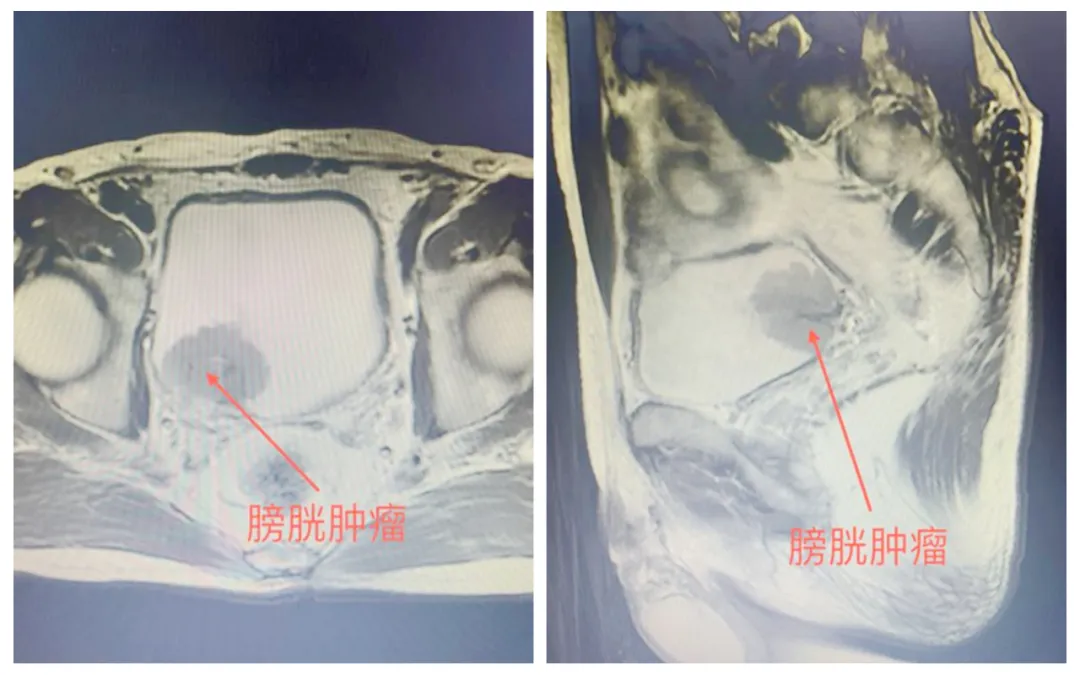

患者入院后完善下腹部+盆腔增强CT提示:膀胱右侧壁占位,考虑膀胱恶性肿瘤并侵犯右侧输尿管膀胱壁内段。进一步完善盆腔增强磁共振提示:膀胱右后壁可见一菜花状向腔内生长软组织肿块,大小约36mmX30mmX35mm,病变覆盖右侧输尿管膀胱壁内段,进一步完善膀胱镜活检提示:膀胱乳头状尿路上皮癌,浸润肌层。患者家属听闻膀胱肿瘤侵犯肌层需切除整个膀胱,并可能需要长期留置造口袋引流尿液后十分担心,向毕学成主任提出能否有好的手术方案,既能达到根治肿瘤的效果,又方便患者术后生活的护理。

▲患者术前盆腔增强磁共振结果